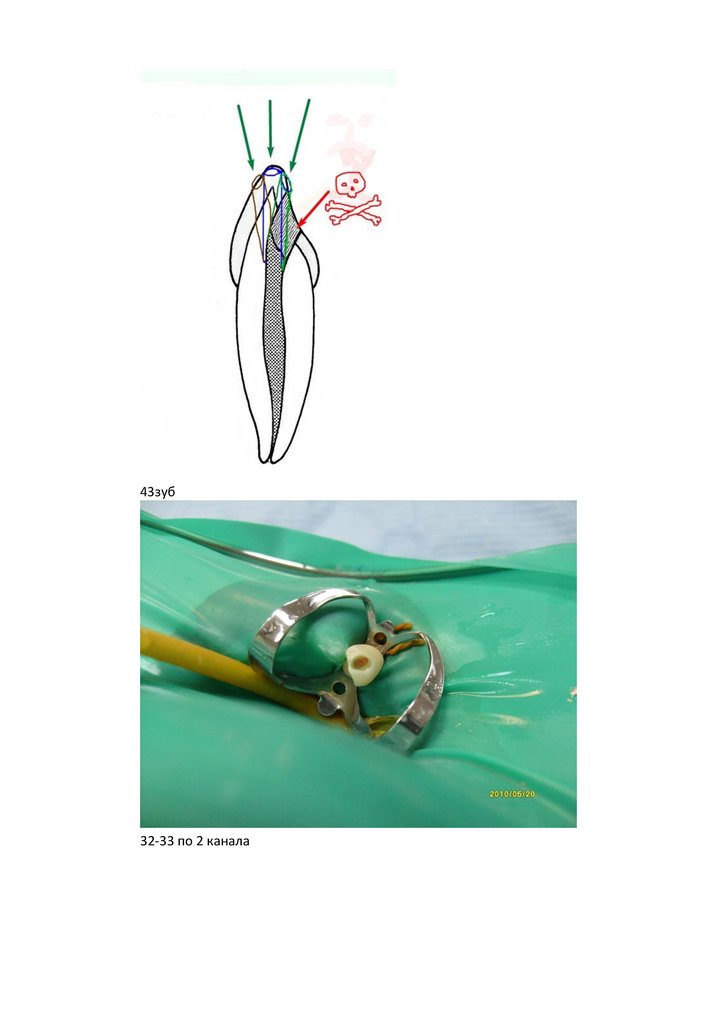

Начну с доступа к каналам. Резцы и клыки в/ч. Вот такой предлагается в литературе.

(картинки взяты из Коэна и Бернса, некоторые мной перерисованы)

При классическом доступе через слепое отверстие получается значительный изгиб,

иногда бывает, что перфорируется вестибулярная стенка, но чаще всего остаются

слепые пространства в пульповой камере с обрывками пульпы отмеченные

красным N.B. Приходится потом бором шариком или обратным конусом

изворачиваться чтоб дообработать-увеличение полости.

Еще нежелательные эффекты: при обработке файлами и ультразвуком в местах

отмеченных синим происходит плотный контакт с тканями зуба, что ведет к

излишнему напряжению на файл + увеличение полости с излишним убиранием

тканей + неоправданно большое истончение дентина в пришеечной области, так

нужного для протезирования + непонятки из-за чего файл так туго крутиться- толи в

канале кончик приклинивает- толи в устье зажимает, а кончик болтается? + сильный

изгиб повышает (особенно при микродоступе) шанс отлома кончика УЗ файла.

Поэтому если депульпируется интактный зуб то полость делается как ниже на

рисунках . Синими точками отмечены начало препарирования, окружностями

примерно получающиеся полости.

Мы получаем почти прямой доступ к каналам, тканей везде остается больше.

Если уже имеется полость или старая пломба то доступ осуществляется как показано

На этих фотках отмечен начавшийся доступ к каналу, он хоть немного, но смещен к

резцовому краю.

В клыке делать полость по режущему краю, на внутреннем скате бугра, или на

внешнем- в зависимости от изгиба коронки.

43зуб

32-33 по 2 канала